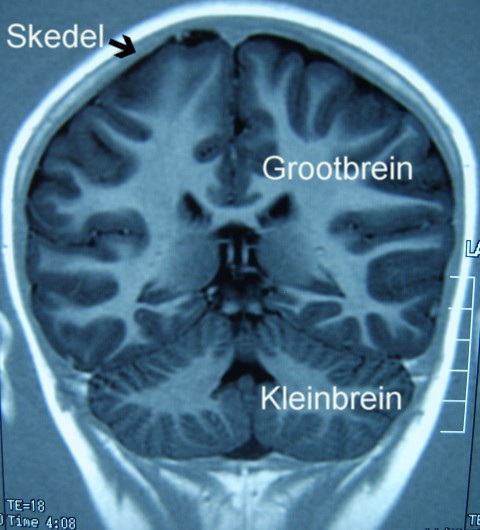

Elke neuron is in verbinding met tot 10 000 ander en dit het tot gevolg dat daar meer elektriese verbindings in een menslike brein is as wat daar in al die elektriese apparate op aarde is. Die brein is baie sensitief vir skade, dus word dit baie nou omsluit deur die kranium of breinkas soos in die magnetiese resonansbeeld hier onder gesien. Terloops: hierdie passing is so intiem dat die patroon van die brein, die voue en gleuwe, ook aan die binnekant van die skedel te sien is.

Magnetiese resonansbeeld (MRI) van die groot- en kleinbrein. Let op die nousluitende aard van die skedelbene.